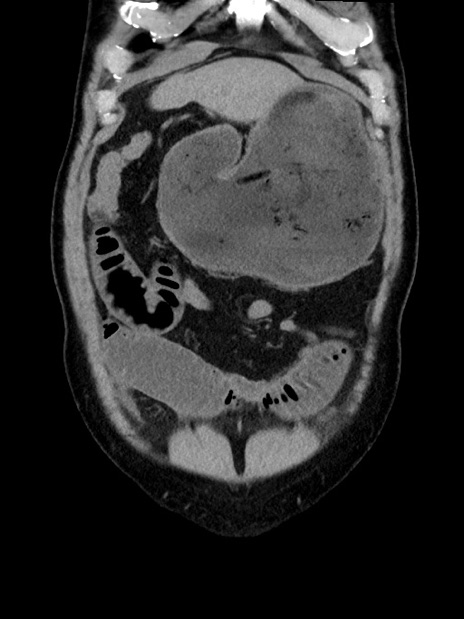

症例35(冠状断像)

【症例】70歳代 男性

【主訴】腹部膨満、嘔吐

【現病歴】昨日より腹部膨満感出現。本日増悪し、仙痛出現。嘔吐あり、受診。

【既往歴】糖尿病、胆摘後

【身体所見】BP 149/80mmHg、HR 74/min、BT 35.9℃、腹部:膨満、軟、圧痛なし。腸雑音減弱あり。上腹部正中切開瘢痕あり。

【データ】WBC 13500、CRP 1.72